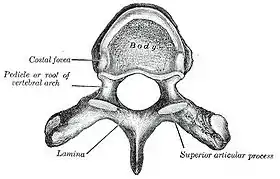

Upper view of a human vertebra, with the laminae visible | |

The lamina is a posterior arch of the vertebral bone lying between the spinous process (which juts out in the middle) and the more lateral pedicles and the transverse processes of each vertebra. The pair of laminae, along with the spinous process, make up the posterior wall of the bony spinal canal. Although the literal meaning of laminectomy is 'excision of the lamina', a conventional laminectomy in neurosurgery and orthopedics involves excision of the supraspinous ligament and some or all of the spinous process. Removal of these structures with an open technique requires disconnecting the many muscles of the back attached to them. A laminectomy performed as a minimal spinal surgery procedure is a tissue-preserving surgery that leaves more of the muscle intact and spares the spinal process. Another procedure, called the laminotomy, is the removal of a mid-portion of one lamina and may be done either with a conventional open technique or in a minimalistic fashion with the use of tubular retractors and endoscopes.